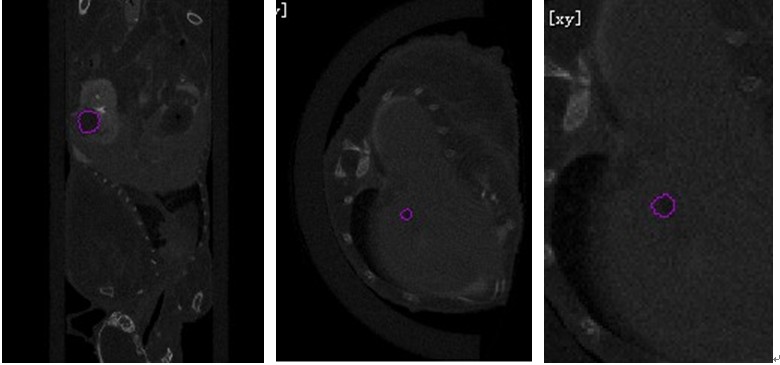

Micro-CT掃描重建結(jié)果如圖3所示,(a)圖中為胃癌腫瘤轉(zhuǎn)移到腎中的腫瘤區(qū)域(紫色線條圈出的區(qū)域),(b)圖為肝中幾個轉(zhuǎn)移灶中的一個微轉(zhuǎn)移灶的腫瘤組織,(c)圖為(b)圖的局部放大圖:

(a)                         (b)                    (c)

圖3 利用臨床碘海醇造影劑造影腫瘤組織與臟器組織對比度增強效果